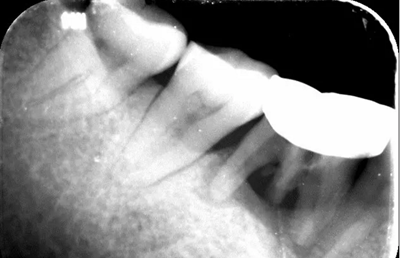

4、術(shù)前根尖片

診斷:46牙根折伴牙槽骨吸收。

治療計(jì)劃:46拔除牙槽嵴保存術(shù),延期種植術(shù)。